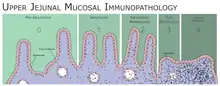

The classic pathology changes of coeliac disease in the small bowel are categorised by the "Marsh classification":[99]

- Marsh stage 0: normal mucosa

- Marsh stage 1: increased number of intra-epithelial lymphocytes (IELs), usually exceeding 20 per 100 enterocytes

- Marsh stage 2: a proliferation of the crypts of Lieberkühn

- Marsh stage 3: partial or complete villous atrophy and crypt hypertrophy[100]

- Marsh stage 4: hypoplasia of the small intestine architecture

Marsh's classification, introduced in 1992, was subsequently modified in 1999 to six stages, where the previous stage 3 was split in three substages.[101] Further studies demonstrated that this system was not always reliable and that the changes observed in coeliac disease could be described in one of three stages:[18][102]

- A representing lymphocytic infiltration with normal villous appearance;

- B1 describing partial villous atrophy; and

- B2 describing complete villous atrophy.